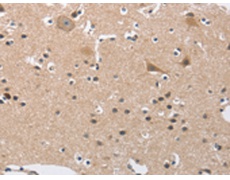

IHC positive control: |

Human brain and human thyroid cancer |